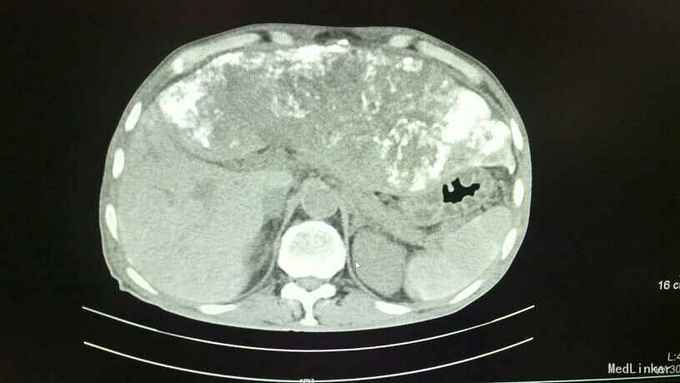

诊断:1、原发性肝细胞癌(巨块型) 2、肝内转移并子灶形成 3、低蛋白血症 4、胸、腹腔积液(少量) 治疗:入院后完善相关常规、生化检查如上述,综合评估病情后考虑患者巨块型肝癌大小约达30*13cm,存在肝癌肿块破裂大出血风险可能性极大,遂立即向其家属告病重。治疗上予护肝、补充白蛋白、护心、补液等对症支持治疗,3日后送手术室行”肝癌血管介入化疗栓塞术(TACE术)“,术中先选取肝动脉,予”氟脲苷+卡铂+平阳霉素+丝裂霉素“向血管行灌注化疗,再予碘化油向血管内灌注以栓塞血管阻断肿瘤血供,再选取肠系膜上动脉,再予上述化疗药物向血管内行灌注化疗。术后患者出现上腹部疼痛、腹胀,食欲严重下降,发热,呈中高热,呕吐数次。均考虑患者介入术后常见不良反应及肝脏及肿块栓塞后液化坏死所致。术后常规予抗感染、护肝、护胃、护心、止呕、补蛋白、适当利尿、维持电解质平衡、加强护理、记24小时尿量等对症支持治疗。病情好转并稳定后复查上腹部CT较入院时缩小,具体见下图所示,提示治疗有效。

随访:随访一月,患者肝左叶巨块型肝癌较前缩小。查体触诊上中腹部可及一肿块大小约24*8cm,于剑突下8cm可触及,于右侧肝肋缘中点下2cm处可触及,质地硬,边缘不规整,表面凹凸不平。 讨论:TACE术:是指将导管选择性或超选择性插入到肿瘤供血靶动脉后,以适当的速度注入适量的栓塞剂,使靶动脉闭塞,引起肿瘤组织的缺血坏死。使用抗癌药物或药物微球进行栓塞可起到化疗性栓塞的作用,称之为TACE。目前最多用于肝癌的治疗,包括: 肝动脉插管化疗栓塞,或肝动脉插管化疗灌注。我们都知道:肿瘤的生长有赖于肿瘤新生血管的形成,当肿瘤生长至一定体积(1~2mm)时,由于缺氧和局部组织PH值的下降,肿瘤便会分泌促血管生成因子,加速肿瘤新生血管的形成,以提供肿瘤生长所需要的氧和营养成分。TACE作为临床治疗肝细胞癌的重要方法,主要通过栓塞肿瘤的供血动脉,阻断肿瘤的血供,导致肿瘤缺血、缺氧,达到抑制肿瘤生长、促使肿瘤细胞坏死、凋亡的目的。适用于原发性或转移性肝癌、肝癌术后复发(肝功能Child分级为A、B-级)、肝血管瘤、肾癌、盆腔肿瘤等的治疗以及鼻咽癌、肺癌、消化道、盆腔肿瘤大出血时的栓塞止血等。 特别是在此例中:患者为73岁高龄的老年患者,又是如此巨块型肝癌,大小约达30*13cm,已经不具备手术指征,因为手术风险性极大,极大可能会因为在术中各种原因导致肝癌破裂而大出血不止却无法抢救,甚至根本抢救不过来!或其他原因记其他不利因素,使得患者及其家属选择保守治疗的。而此时,TACE术就特别适用于这一类患者,既可以收到一定的疗效也可以缓解病情进展,延缓生命,改善生活质量。并且TACE术还可以按照这个原理扩展到其他的肿瘤类型,比如肺癌,直肠癌,妇科恶性肿瘤,胃癌等等,均可以尝试行动脉灌注化疗,亦可以称之为局部化疗。比起全身静脉化疗,此法可以使病灶(肿瘤)更局限更集中吸收化疗药,再辅以差价量化疗会取得不错的效果。